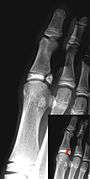

Salter–Harris fracture images

| Salter–Harris fracture radiographs with insets showing fracture lines. | ||||||||